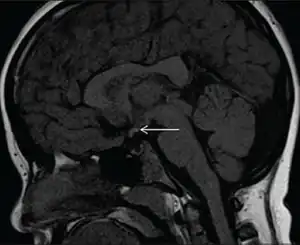

Diagnostic method | MRI scan |

Pituitary stalk interruption syndrome (PSIS) is a congenital disorder characterised by the triad of an absent or exceedingly thin pituitary stalk, an ectopic or absent posterior pituitary and/or absent or hypoplastic anterior pituitary.[1][2]